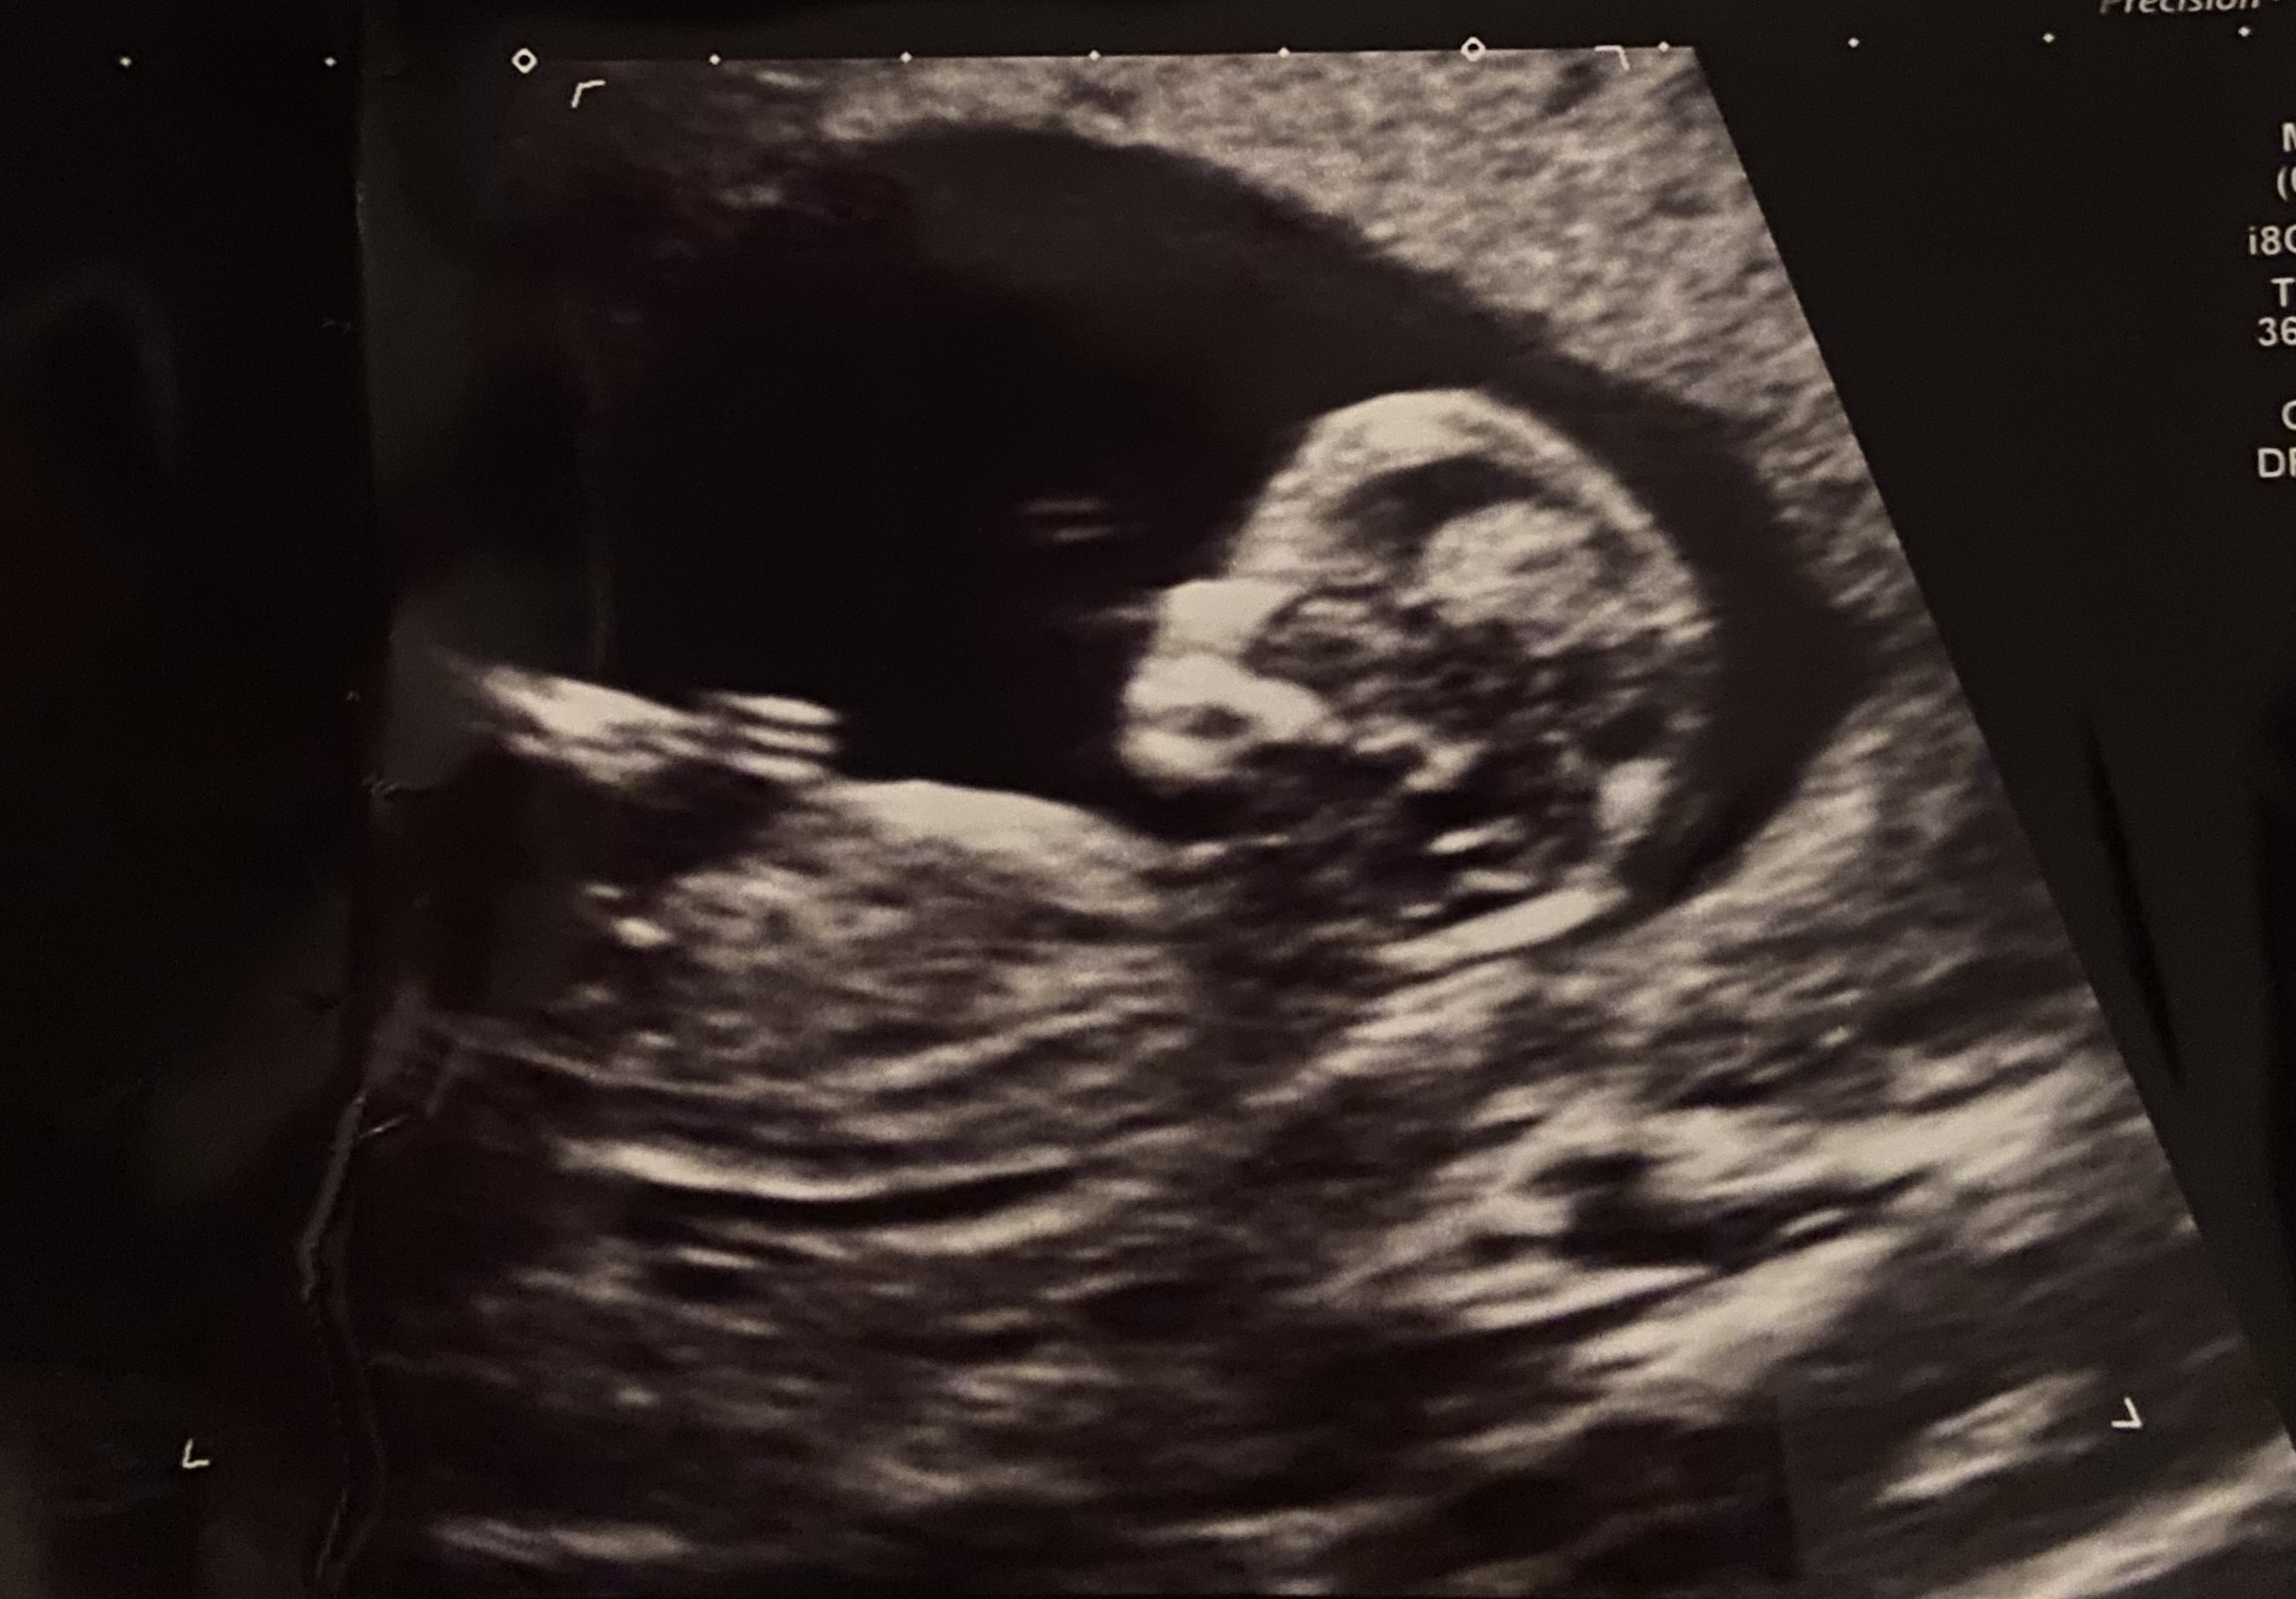

We had two more betas, including a first ultrasound to check for placement of the gestational sac. And then on October 27th, we saw a fetal pole and a baby for the first time.

Since then baby has been growing steadily. Their heartbeat sits in the 150s most days.

They are healthy and getting bigger and bigger every day.

We are due June 18, 2026, and we can’t wait to meet them.